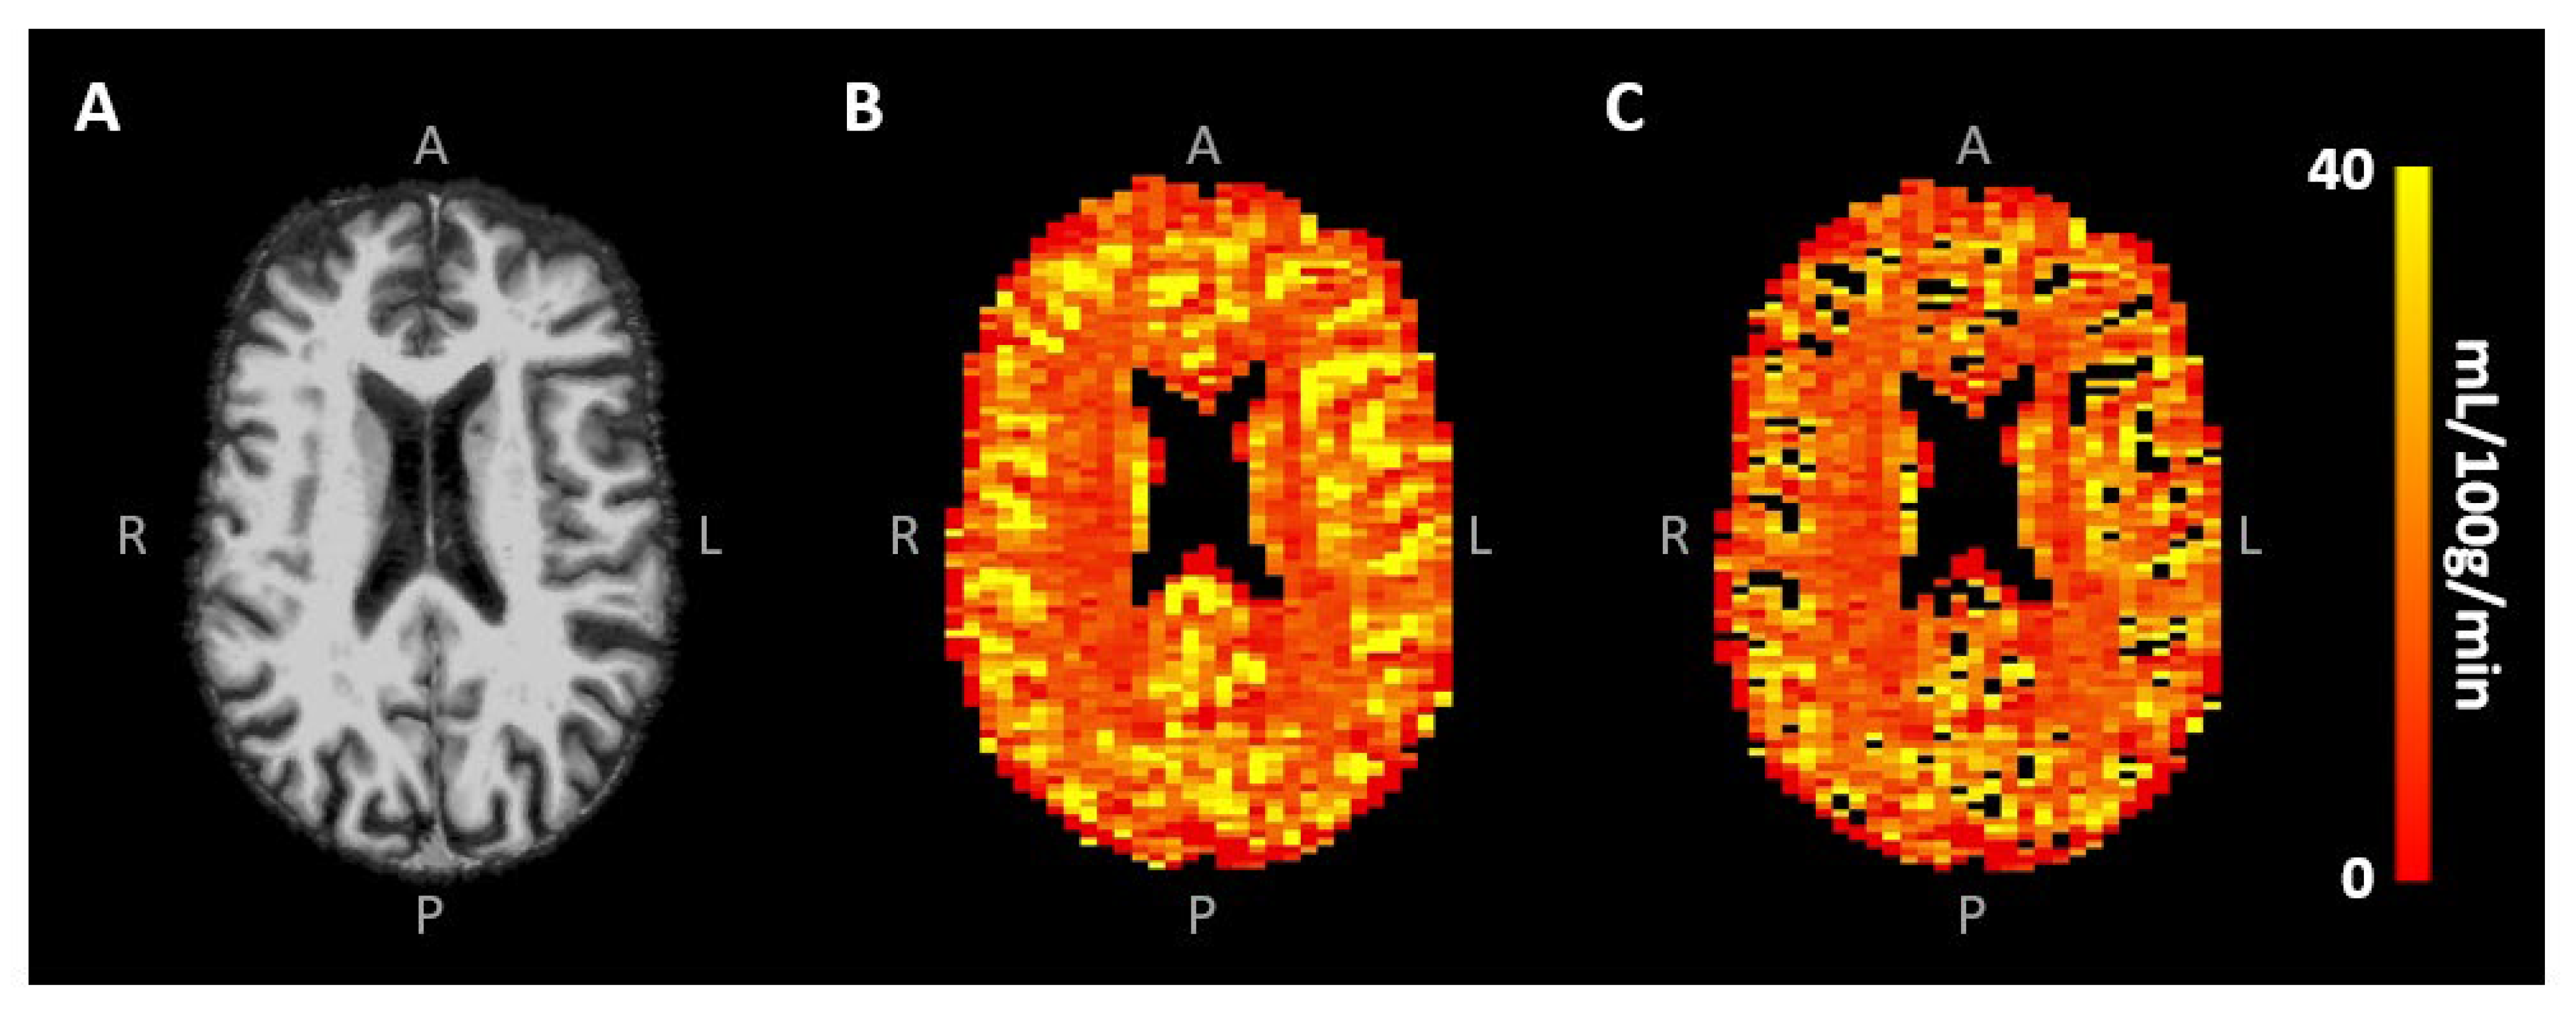

2.3.2. SE-EPI DSC-MRI